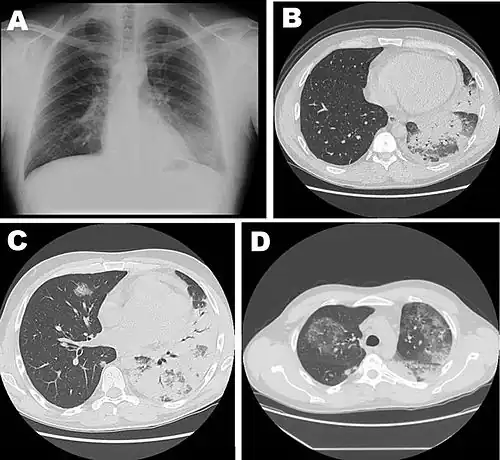

![]() | |

| Chest X-ray of a severe case of legionellosis upon admission to the emergency department | |

Laboratory tests may show that kidney functions, liver functions, and electrolyte levels are abnormal, which may include low sodium in the blood. Chest X-rays often show pneumonia with consolidation in the bottom portion of both lungs. Distinguishing Legionnaires' disease from other types of pneumonia by symptoms or radiologic findings alone is difficult; other tests are required for definitive diagnosis.